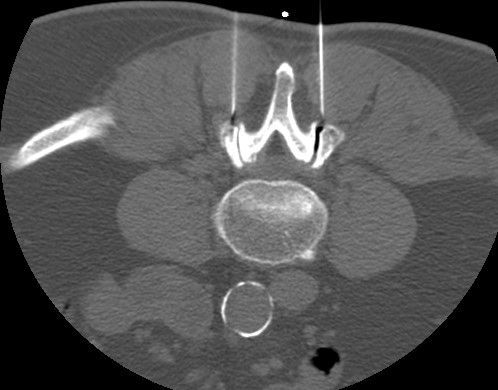

Wir bieten die PRT in Darmstadt für die Lendenwirbelsäule (LWS) an. Dabei wird unter CT-Kontrolle eine Injektionskanüle bis an die austretende Nervenwurzel herangeführt, in der Nähe der Nervenwurzel platziert und es wird ein Medikamentengemisch aus Cortison und örtlichem Betäubungsmittel direkt an die Nervenwurzel gespritzt. Unser Ziel ist es, die an der Nervenwurzel bestehende Entzündungsreaktion und die dadurch entstandenen Schmerzen zu lindern.

Bei der Facettengelenksinfiltration / Facettenblockade handelt es sich um eine weitere spezielle Form der Schmerztherapie. Dabei wird unter CT-Kontrolle eine Injektionskanüle bis an die kleinen Zwischenwirbelgelenke herangeführt und ein Medikamentengemisch aus Cortison und örtlichem Betäubungsmittel gespritzt.